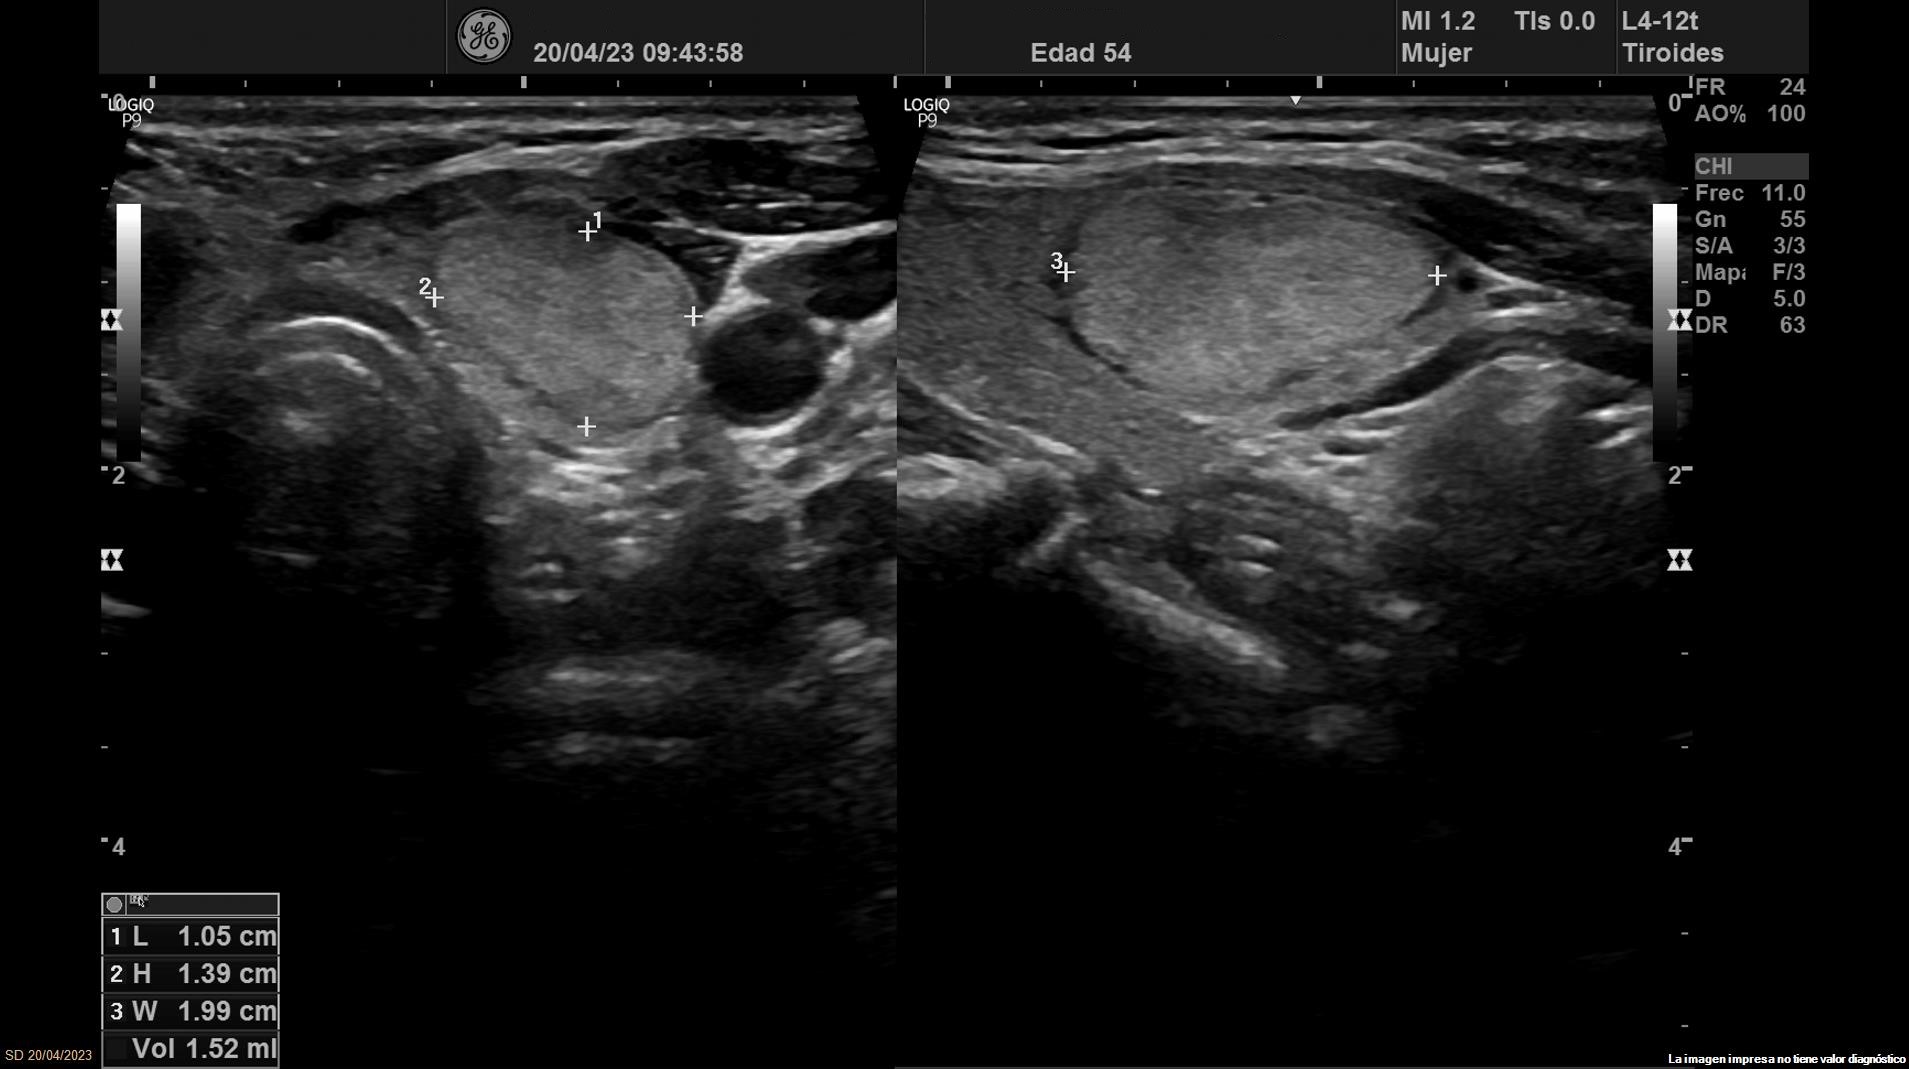

Se objetiva una adenopatía de 0,8 cm de aspecto benigno, ovalada y con bordes definidos. Además, se realiza ecografía tiroidea:

• Lóbulo tiroideo izquierdo: tamaño normal. En la mitad inferior se objetiva un nódulo de 11 x 14 x 20 mm (Vol 1,52 ml), bien definido, sólido e iso/hiperecoico, con halo fino hipoecoico, sin calcio y con vascularización de predominio periférico (ATA: baja sospecha).